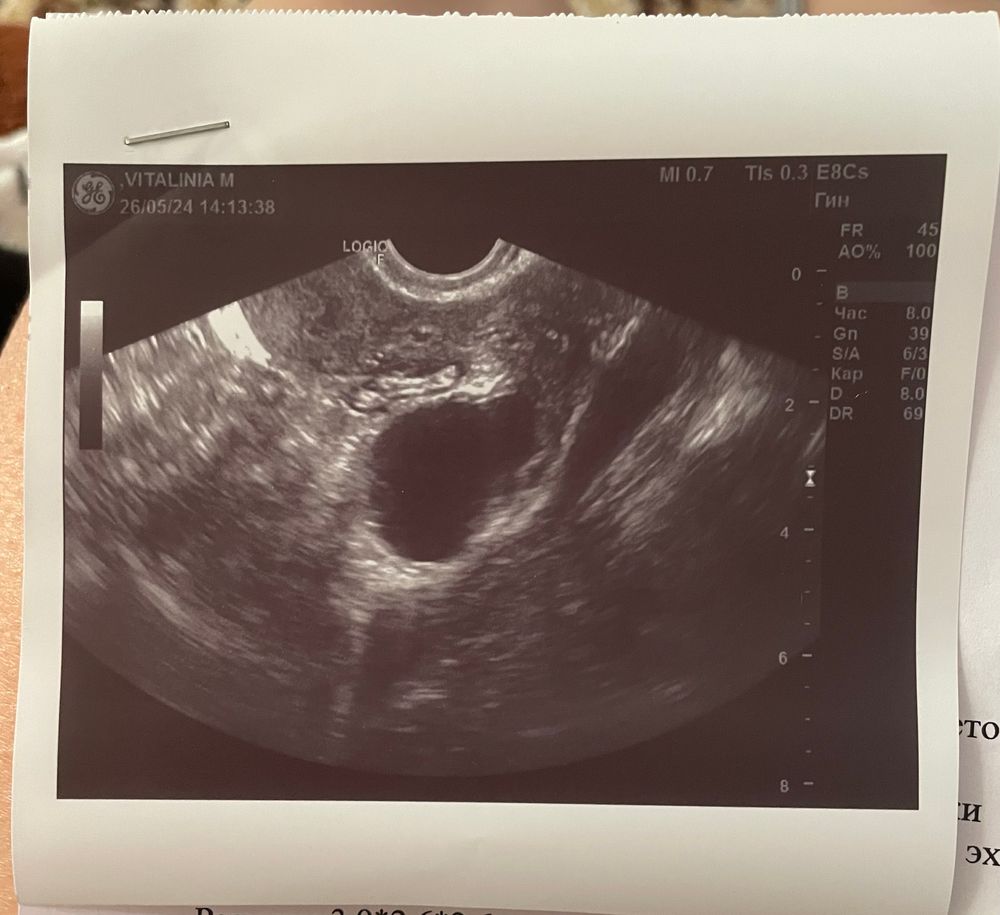

Подскажите это значит овуляция была или нет?

На первом узи типо овуляция только должна быть,а на втором типо была.Пишет что Киста жёлтого тела и есть жидкость,что указывает на то,что овуляция произошла 🙂

Да, конечно, судя по второму УЗИ овкляция у Вас была, да и эндометрий подрос) удачи Вам в этом цикле. У нас с Вами рядом циклы, будем надеяться)